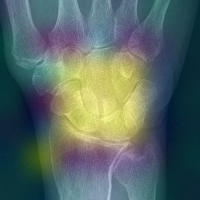

Refer to caption

(c) Wrist

Figure 4: Attention weights corresponding to various joints while predicting narrowing scores from extracted fingers and wrists from the radiographs, yellow regions demonstrate the region where the model assigns higher weights in the input image

In Fig. 5(a), and 5(b), the joint region in the feet and hand fingers is activated to provide the final predictions, similarly, we see that in Fig. 5(c), all wrist joints are given a higher weightage by the model while making the predictions. Our attention map provides an inbuilt explanability component which can aid the radiologist to believe in the model predictions.